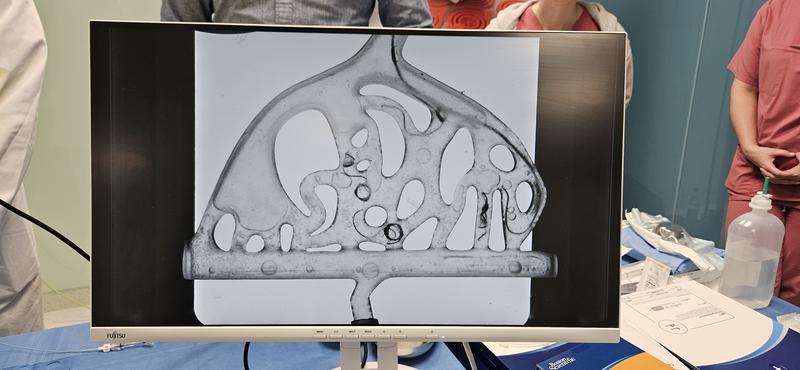

In the MakerSpace, models of human vascular structures were created using 3D printers, with an integrated variable pump system. This system simulates human arterial blood pressure, flow rates, and physiological conditions encountered during real procedures. “After several prototypes, we developed a version that could accurately replicate a transparent, flexible vascular system,” reports Prof. Dr. Thomas Rausch, a key contributor to the project. This enables trainees to safely practice handling instruments such as catheters and guidewires and using coils (spirals) for closure. Prof. Radeleff adds: “Our MANTA phantom prepares medical professionals for emergencies and enhances their responsiveness and precision during urgent medical interventions. Training scenarios such as acute vascular occlusions or arterial bleeding allow interventional radiologists to act faster and more accurately.”

The simplicity and affordability of the model, originally developed using a 3D printer and a storage container, are key advantages that increase the accessibility of training for a broader range of medical students. “The material costs for the model are approximately €250. Additionally, all components can be produced with equipment commonly available in university environments,” says Prof. Dr. Anke Müller. Plans include making the technology available as an open-source guide for other training institutions and university hospitals, in line with the maker movement.